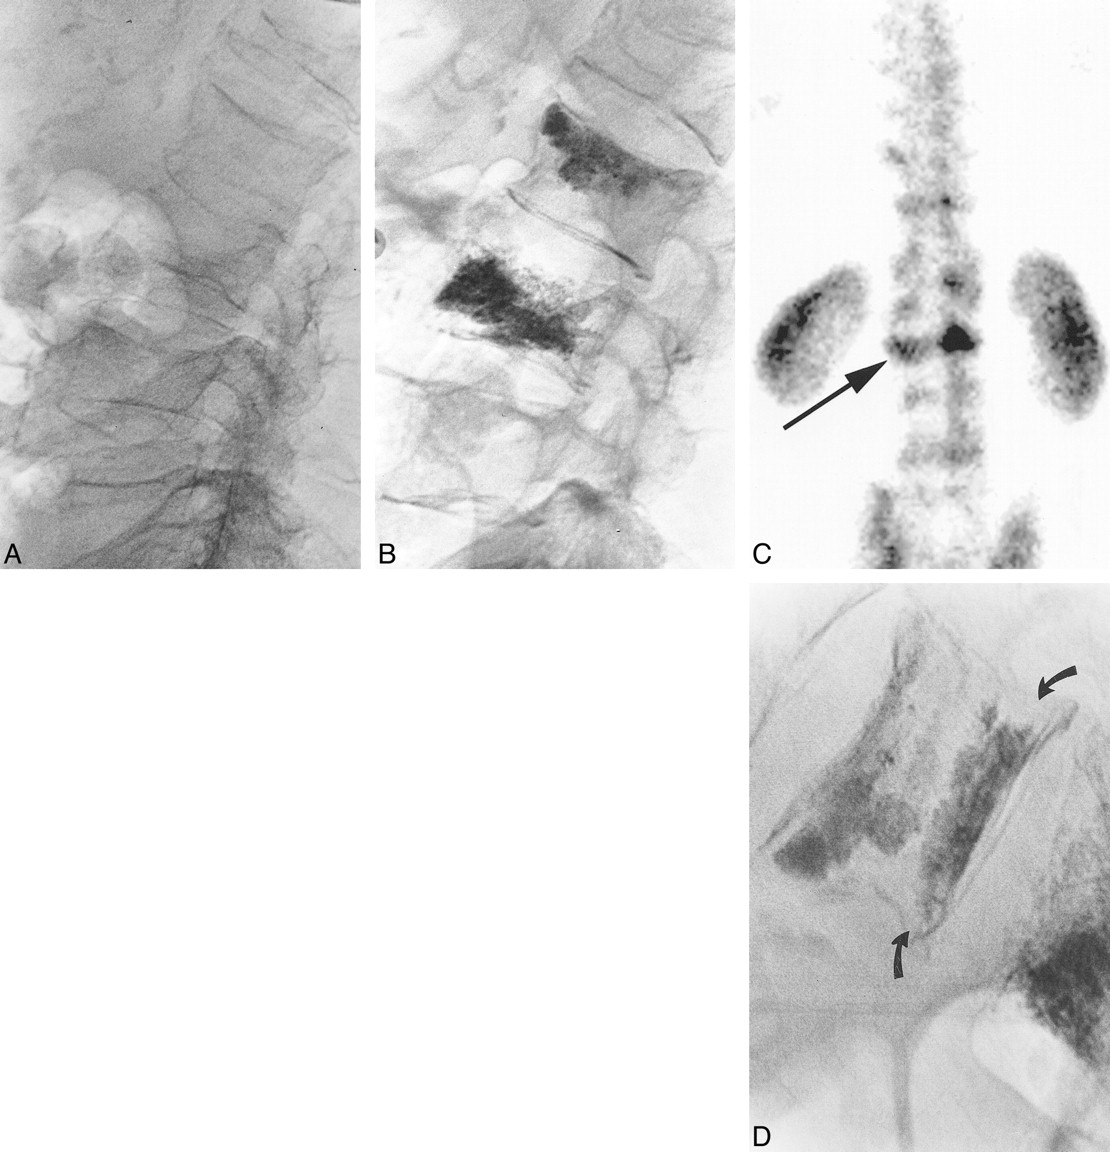

Images from the case of a 77-year-old man who presented with back pain of 3 months' duration.

A, Lateral view plain film radiograph obtained over the lumbar spine shows fractures at L1–L5. No previous images were available to date the onset of fracture at any level. However, because the patient experienced focal tenderness over the spinous processes of L2 and L3 without tenderness over the other fracture levels, we elected to proceed with vertebroplasty at L2 and L3, without performing preprocedural bone scan imaging.

B, Postprocedural lateral view plain film radiograph obtained over the lumbar spine shows barium-opacified methylmethacrylate within the L2 and L3 vertebral bodies. Cement injection at L3 traversed the entire marrow cavity. Cement selectively traversed the superior endplate region at L2, which is commonly seen as the cement naturally extends into fracture lines. Subjectively, the patient improved “about 50 percent,” but he requested further treatment, if possible. Bone scan imaging was performed because of uncertainty regarding further therapy.

C, Posterior planar Tc99m-MDP2 bone scan shows increased activity in the region of the L2 fracture (arrow). Based on the bone scan image, which suggested ongoing bone turnover in L2, we selectively targeted the inferior aspect of L2 for the second vertebroplasty treatment.

D, Postprocedural lateral view plain film radiograph shows barium-opacified methylmethacrylate within the inferior aspect of L2 (curved arrows). The patient noted complete pain relief after the second vertebroplasty at L2, stating that he felt “the best he has felt in years.”